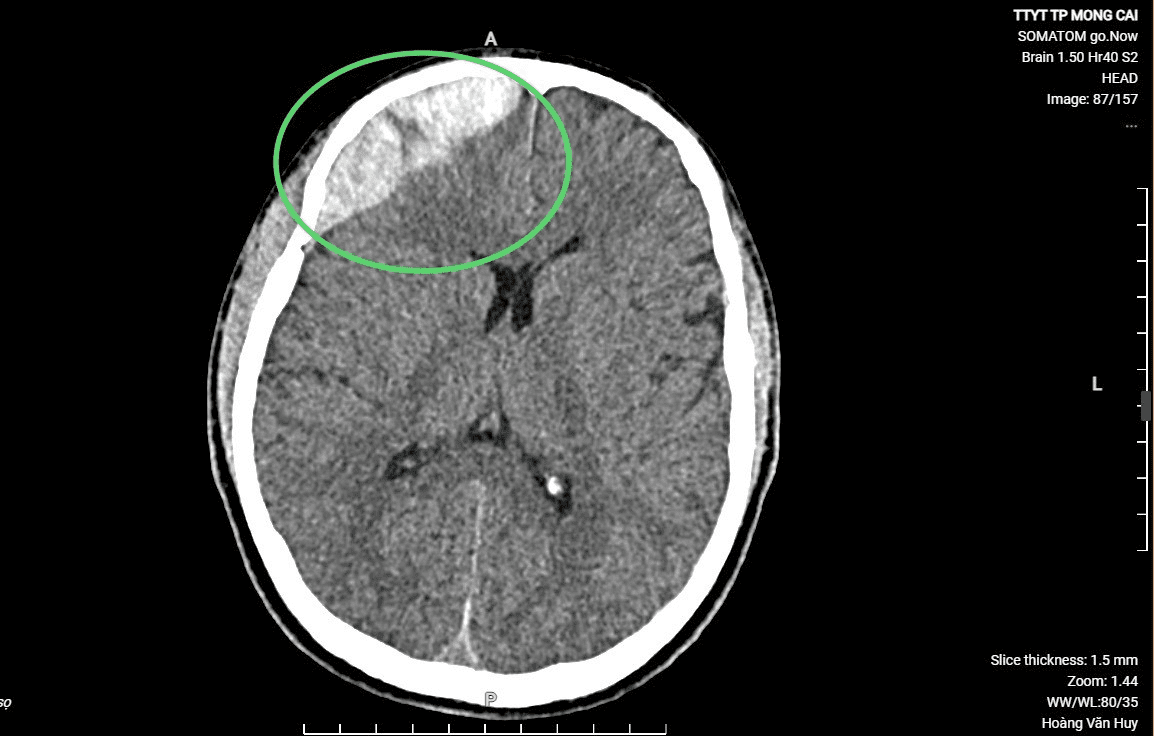

Hình ảnh chụp CT trước và sau khi phẫu thuật

Bệnh nhân được tiến hành phẫu thuật mở hộp sọ, lấy máu tụ trong não, cầm máu, sau hai ngày phẫu thuận, bệnh nhân tỉnh, không liệt, đã ngồi dậy bắt đầu tập phục hồi chức năng. Sau 7 ngày, bệnh nhân đã hoàn toàn tỉnh táo, bình phục gần như hoàn toàn.